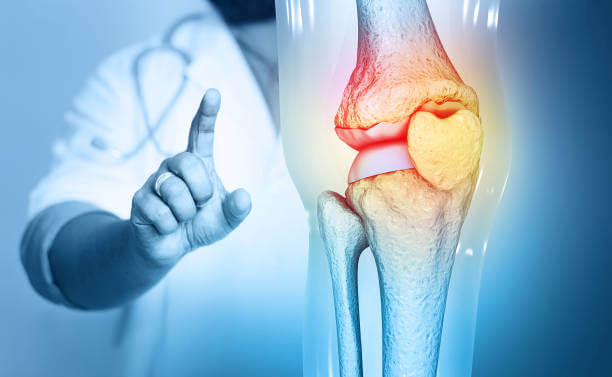

류마티스 관절염은 자가면역체계에 이상이 생기면서 발생하게 되는 질환입니다. 류마티스 관절염은 관절이나 힘줄을 둘러싸고 있는 활액막에 염증이 생기면서 발생하게 됩니다.

류마티스 관절염은 관절에만 염증이 생기는 것이 아닌 신체 여러 곳에서 염증이 생기게 되는 염증성 질환입니다.

류마티스 관절염의 증상

류마티스 관절염의 경우 증상이 개인별로 다를 수 있습니다. 많은 증상 중에서 가장 많이 발생하는 증상으로는 한두개의 관절이 붓고 아프며 손끝의 관절보다는 첫번째나 중간에 있는 관절에서 염증이 생기게 됩니다.

류마티스 관절염은 초기에 손가락 관절이나 손목관절에서 많이 생기며 관절염이 진행되면서 팔꿈치, 발목, 어깨, 무릎관절에서도 나타날 수 있는 질환입니다.